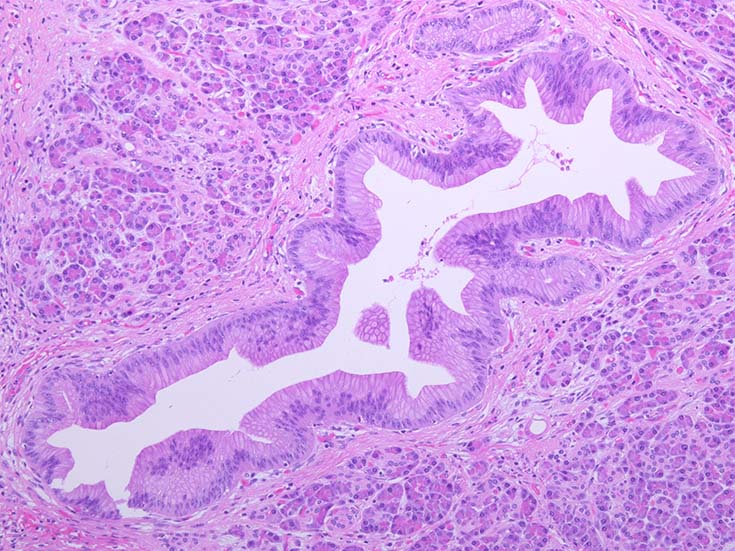

膵上皮内腫瘍性病変 pancreatic intraductal neoplasm(PanIN)*16

Low-grade PanINとhigh-grade PanINの分類

high-grade PanIN

PanINの図譜はJohns Hopkins The Sol Goldman Pancreatic Cancer Research CenterのHome page*19から引用.

2. PanIN-2, PanIN-3;

• TP53の不活化--PanINでのIHCでは機能喪失が,PanIN3のみで観察される. 膵癌発がん過程の遅い段階に出現する事象.

• SMAD4の不活化--PanIN3の30%で発現陰性化. PanIN-1,2では, SMAD4免疫染色は陽性. 発現の陰性化は後期PanINで発現する重要な異常*20.